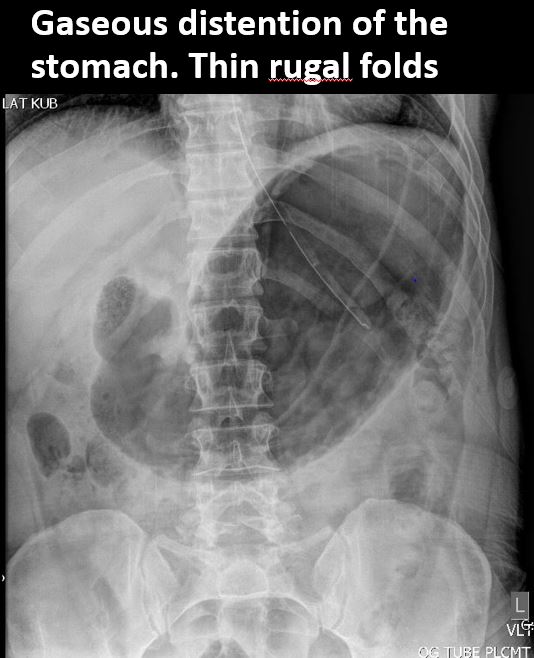

​The stomach is distended with gas or fluid.

​There is thickening of the wall of the stomach.